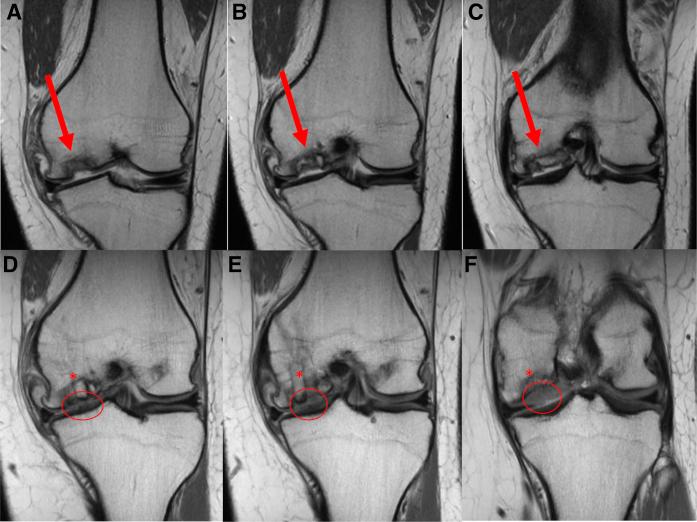

使用预切割骨软骨异体移植塞和微粉化细胞外软骨增强技术进行供区回填的膝关节局灶性软骨损伤自体骨软骨移植术

Osteochondral Autograft Transfer for Focal Cartilage Lesions of the Knee With Donor-Site Back-Fill Using Precut Osteochondral Allograft Plugs and Micronized Extracellular Cartilage Augmentation.

Osteochondral autograft transfer (OAT) allows for the treatment of focal chondral lesions of the femoral condyles. Patients undergoing OAT have been shown to have the greatest rate and quickest return to sport of any cartilage-restoration procedure. Disadvantages encountered with the OAT procedure include limited donor sources, small treatable lesion size, and donor-site morbidity. Here, we describe our preferred technique of open OAT with donor-site back-filling using precut fresh osteochondral allograft plugs and micronized extracellular cartilage augmentation. Advantages to this technique include single-stage transfer of living autologous osteochondral grafts allowing for early ambulation, predictable return to sport, enhanced long-term graft survival, and decreased donor-site morbidity secondary to fresh osteochondral allograft back-fill.

自体骨软骨移植(OAT)可用于治疗股骨髁的局灶性软骨损伤。接受OAT治疗的患者在所有软骨修复手术中恢复运动的比例最高且恢复速度最快。OAT手术存在的缺点包括供体来源有限、可治疗的损伤面积小以及供体部位的并发症。在此,我们描述了一种开放式OAT的首选技术,即使用预先切割的新鲜骨软骨同种异体移植栓进行供体部位回填以及微粉化细胞外软骨增强。该技术的优点包括单阶段移植活的自体骨软骨移植物,允许早期下床活动、可预测的运动恢复、提高移植物长期存活率,以及因新鲜骨软骨同种异体移植回填而降低供体部位并发症。